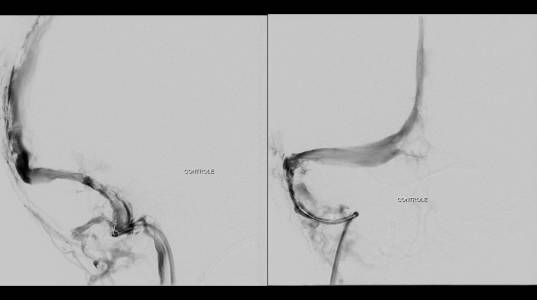

Foi realizada discussão entre as diversas especialidades, em vista da não melhora com o uso do anticoagulante, foi sugerido a tentativa de trombectomia mecânica do seio dural.

O caso clínico apresenta a utilização de materiais com finalidades primárias para trombectomia mecânica no contexto de acidente vascular cerebral (Rebar 27 + Solitaire) e o balão Copernic RC (Balt) comumente utilizado auxiliando na embolização de fístulas durais para os seios, auxiliando no processo de trombectomia mecânica no contexto de extensa trombose venosa cerebral.